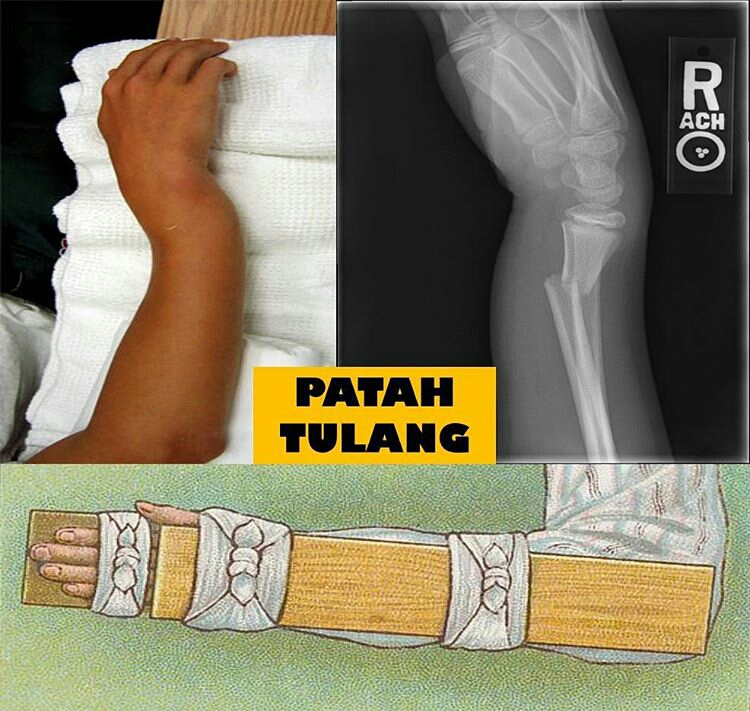

Patah Tulang Jangan Diurut

Patah Tulang Jangan Diurut

Cuti Sekolah dan Patah Tulang Lengan û Dr Ahmad Mahyuddin | The Malaysian Medical Gazette

Cuti Sekolah dan Patah Tulang Lengan û Dr Ahmad Mahyuddin | The Malaysian Medical Gazette